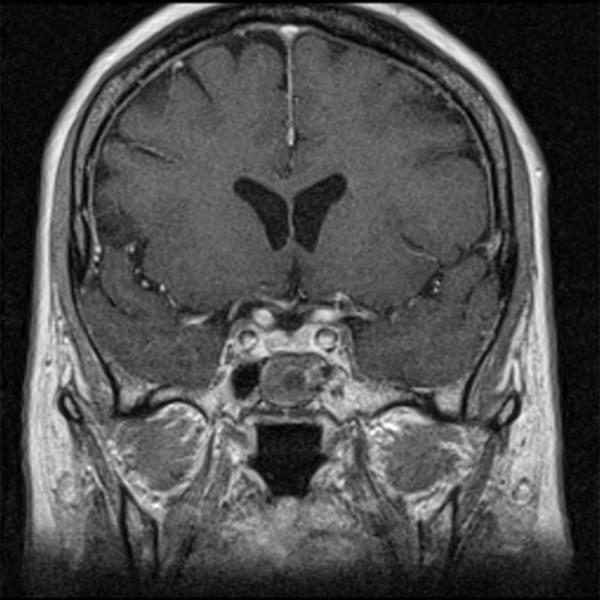

The proper diagnosis and management of patients after surgery for pituitary tumors are of great importance in clinical practice. The purpose of this study was to investigate the magnetic resonance features of the postoperative sella with fast spin echo T2-weighted imaging and to evaluate the benefits of this sequence compared to the classically performed contrast-enhanced T1-weighted imaging at 1.5T unit.

Contrast-enhanced T1-weighted imaging was significantly superior to T2-weighted imaging in assessment of infundibulum (p<0.05). There was no statistically significant difference for each of readers between T1- and T2-weighted images regarding to the following features: visualization of residual pituitary gland (p = 0.062 and p = 0.368), contours of pituitary (p = 0.959 and p = 0.265), optic chiasm (p = 0.294 and p = 0.843), and visualization of presence of residual tumor (p = 0.204 and p = 0.169). T2-weighted images were significantly superior to contrast-enhanced T1-weighted imaging with regard to visualization of contours of residual tumors (p<0.05).

CONCLUSIONS

T2-weighted images may help to discriminate tumorous from non-tumorous involvement of the postoperative sella and the sphenoid sinus. T2-weighted images are also very useful for a long time after the resection in the postoperative evaluation of the implanted muscle with fascia.

在临床实践中,对垂体瘤术后患者的正确诊断和管理非常重要。本研究的目的是探讨快速自旋回波 T2 加权成像在术后鞍区的磁共振特征,并评估该序列与 1.5T 单位常规进行的增强 T1 加权成像相比的优势。

增强 T1 加权成像在评估漏斗方面明显优于 T2 加权成像(p<0.05)。对于每个读者来说,T1 加权和 T2 加权图像在以下特征方面的表现没有统计学差异:残留垂体的可视化(p=0.062 和 p=0.368)、垂体轮廓(p=0.959 和 p=0.265)、视交叉(p=0.294 和 p=0.843)和残留肿瘤的可视化(p=0.204 和 p=0.169)。T2 加权成像在显示残余肿瘤的轮廓方面明显优于增强 T1 加权成像(p<0.05)。

结论

T2 加权图像可能有助于区分术后鞍区和蝶窦中肿瘤性和非肿瘤性病变。T2 加权图像在切除术后植入的肌肉和筋膜的长期随访中也非常有用。